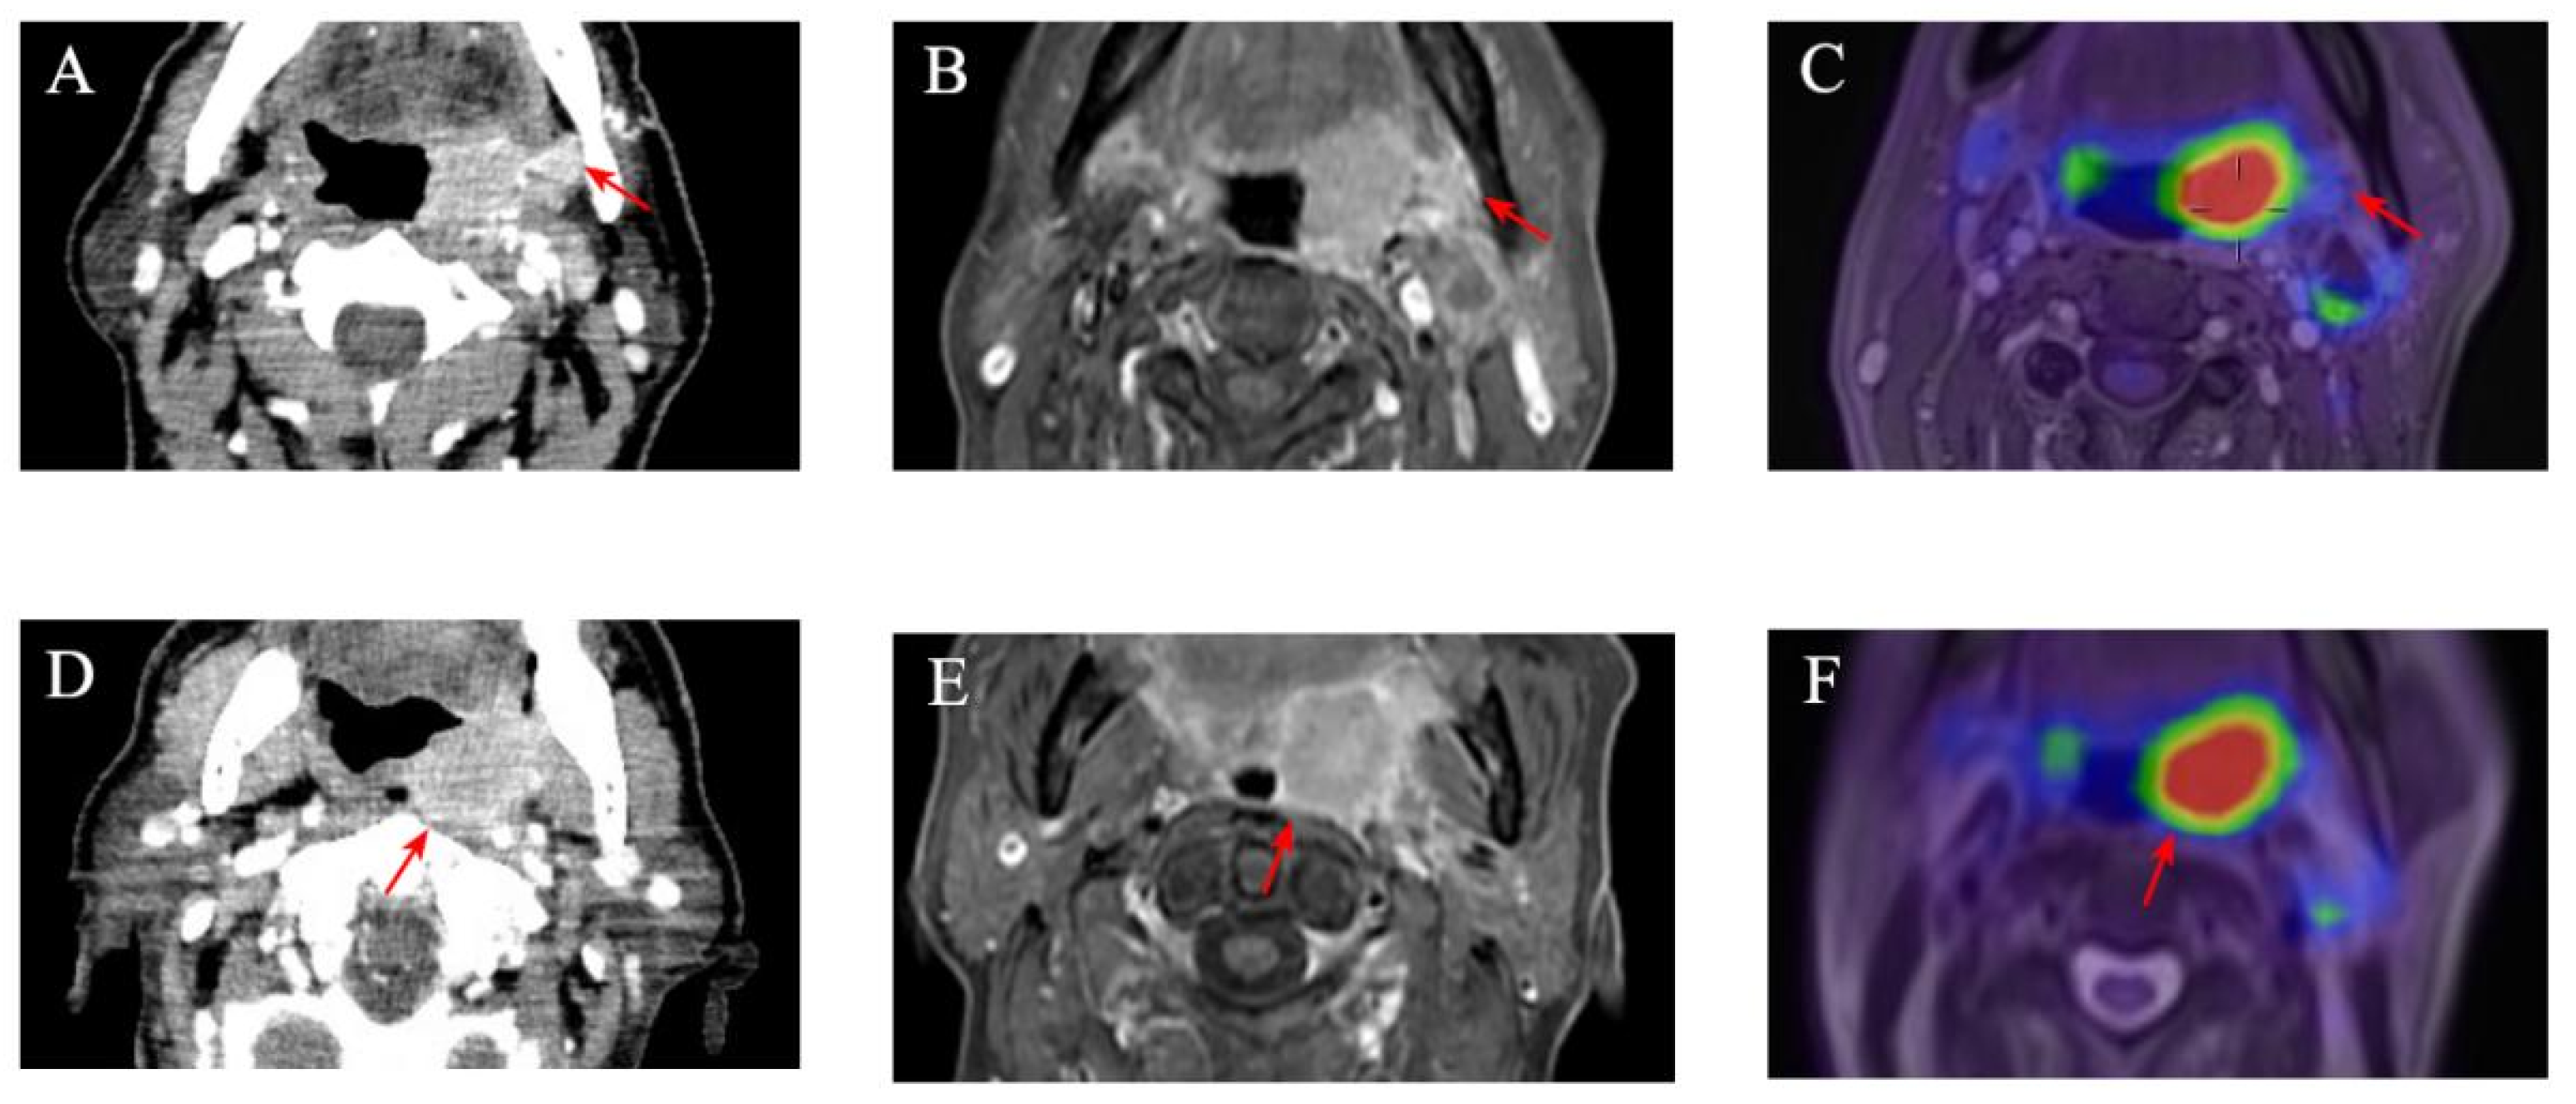

2.2. Imaging

2.3. Imaging Analysis